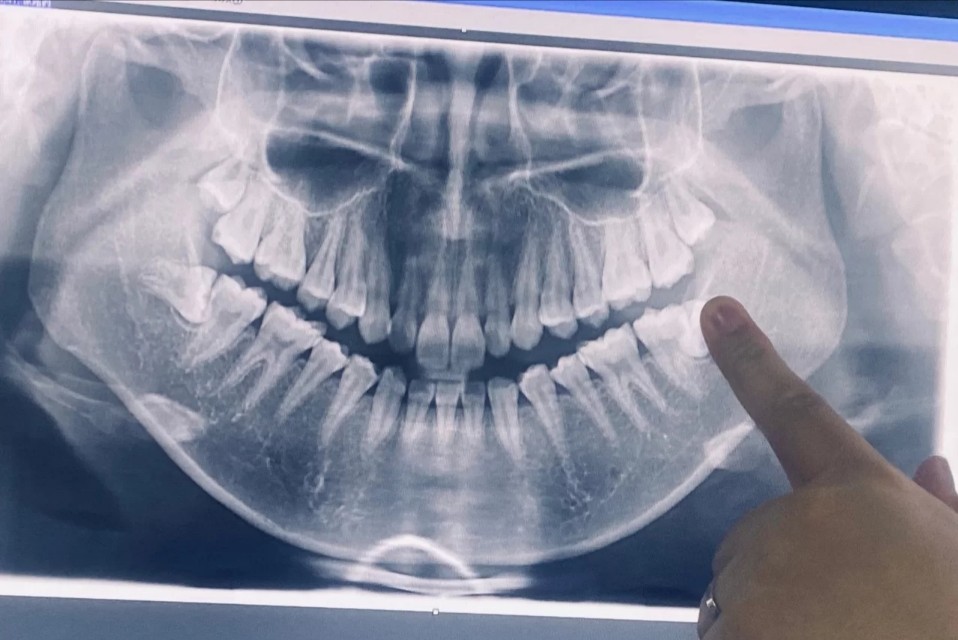

我找了网图,差不多的,还是要文字说明一下:⬇️

‼️下面的两颗智齿,都是横着长的阻生齿,半露出来,上面都是竖着长的普通牙齿

2⃣一大早就出发了,一楼挂号,六楼等着,大概等了一个多小时,然后要拍牙齿全景x照片(35元自费),拍照在二楼,等了十几分钟,拍好就可以立马回去,唐医生和护士门都很好很温柔,看完x片问我先拔哪边,我说左边,然后和我确认了价格,说1500左右,上颗牙齿200一颗,下面要1300左右(微创拔牙),我之前查过所以价格能接受,就签了字!